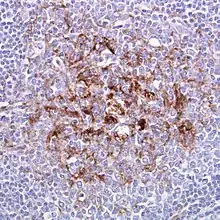

| Biopsy of the tonsil in variant CJD. Prion protein immunostaining. | |

Examination of brain tissue is required to confirm a diagnosis of variant CJD.[2] The following confirmatory features should be present:[2]

- Numerous widespread kuru-type amyloid plaques surrounded by vacuoles in both the cerebellum and cerebrum – florid plaques.[2]

- Spongiform change and extensive prion protein deposition shown by immunohistochemistry throughout the cerebellum and cerebrum.[2]